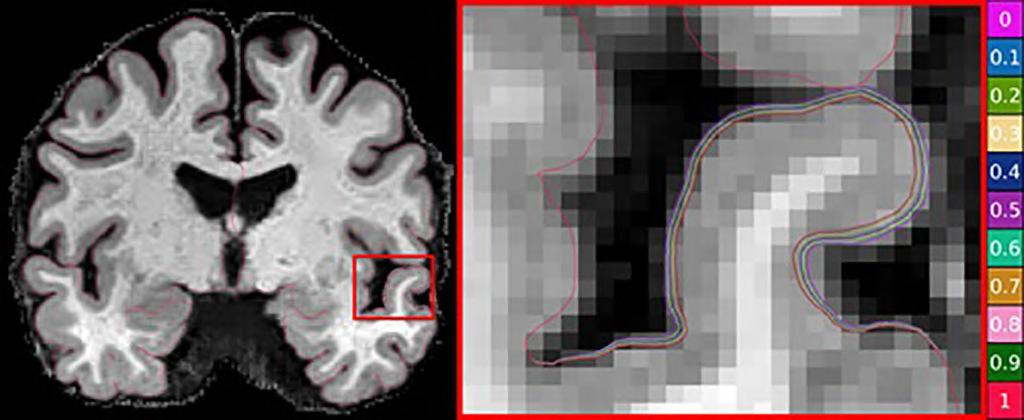

AI-Aided MRI Helps Measure Brain Atrophy

Alzheimer’s is the most common form of dementia and accounts for 60% to 80% of cases. One way to measure its progress is via magnetic resonance imaging (MRI) images that show cortical thinning. However, assessing the onset and progression of Alzheimer’s using brain MRI poses a challenge as changes in the thickness of the brain's cortex are extremely small, usually in the sub-millimeter range. Advanced machine learning techniques are generally used for brain research to examine changes in cortical thickness, although the absence of a clinically accurate ‘ground truth’ dataset meant that their sensitivity to the detection of small atrophy levels could not be evaluated. Until now, the only way to obtain a ground truth measure of cortical thickness was by studying the brain post-mortem. However, this again poses a challenge as the brain begins to shrink immediately after death, resulting in inaccurate readings.

Now, scientists from CSIRO (Canberra, Australia; www.csiro.au), in partnership with Queensland University of Technology (Brisbane, Australia; www.qut.edu.au), have used artificial intelligence (AI) to develop a world-first benchmark for measuring brain atrophy – or thinning - in neurodegenerative diseases, including Alzheimer’s disease. Cortical atrophy – thinning of the brain’s cortex – can begin up to 10 years before the appearance of clinical symptoms of Alzheimer’s disease. The new technique allows researchers to set the amount and location of brain degeneration they wish to compare against in order to achieve a clear picture of the best method for cortical thickness quantification. The technique can test the sensitivity of methods to a miniscule level and determine if a method can detect changes in thickness of just 0.01 millimeters.

The scientists believe they have strong evidence that DL+DiReCT – a deep learning-based method for measuring cortical thickness – is robust and sensitive to subtle changes in atrophy. The technique can be applied to research in any brain disease involving neurodegeneration and marks a significant step forward in better understanding dementia and other debili tating brain diseases. The technique could also be used to predict the level

of cortical degeneration expected in a person over time. The technology was developed on the back of the commonly used and relatively inexpensive MRI images. The researchers have made the synthetic dataset images publicly available for clinicians and scientists who can use the synthetic images to perform their own assessments of cortical thickness quantification methods.

“Using the power of machine learning, we

were able to produce a set of artificial MRI images of brains with predefined signs of neurodegeneration in the cortex region, the outer layer of the brain most affected by Alzheimer’s,” said Filip Rusak, research scientist from CSIRO’s Australian e-Health Research Centre. “Before these findings, there was no way to conclusively determine the sensitivity of the various methods used to measure cortical thickness in Alzheimer’s patients.”